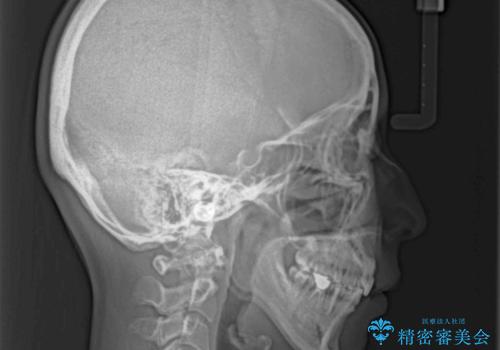

奥歯の咬み合わせ改善には1年ほどの期間と処置中の噛みにくさを強いることとなりましたが、抜歯後はスムーズに治療を完了させることができました。

歯ぎしりの際に奥歯が干渉していた咬み合わせも理想的な状態に改善できました。